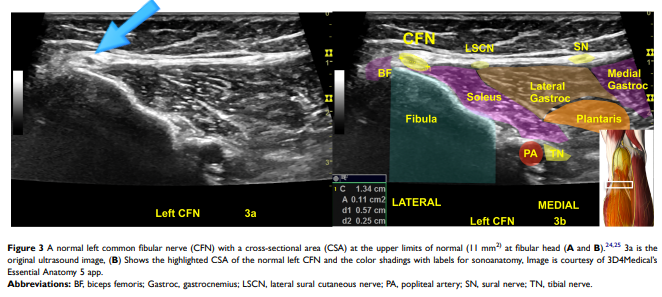

그렇다면 병든 신경은 어떻게 생겼을까요?** 초음파로 들여다보면, 크게 두 가지 모습을 하고 있습니다. 첫 번째는 '퉁퉁 부은 신경'입니다.

@ http://doi.org/10.2147/JPR.S247208 위 사진은 건강한 비골신경으로 단면적은 11mm²이고,

@ http://doi.org/10.2147/JPR.S247208 위 두번째 사진은 손상된 비골신경으로 면적이 22mm²으로 한눈에 봐도 전체적으로 퉁퉁 부어서 두 배 가까이 커져 있는 게 보이시죠? 스트레스를 받은 신경이 부어오른 겁니다.